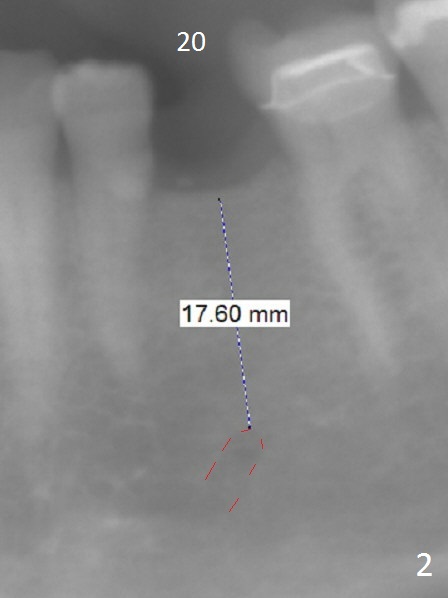

A 54-year-old woman has good oral hygiene.  Panoramic X-ray shows generalized long roots, which suggest bruxism (Fig.1).  Since the bone height is sufficient, a long implant will be placed, probably 4x13 mm (Fig.2).  Take photos of the edentulous space, concentrating on the ridge top.  Flap surgery will be performed.  Crestal bone is going to be reduced if the ridge is narrow.  PA is taken after 1.6 mm drill for 11 mm.  If the trajectory is correct, a 3.3 mm Magic Drill is to be used (13 mm stopper, after Marking bur), followed by 4x11 mm dummy implant.  If the bone is dense, a final drill will be used for 14 mm before placement of the definitive implant.  The harvested autogenous bone will be placed around a pair abutment to increase the buccolingual width.  Take postop photos to show the ridge augmentation.